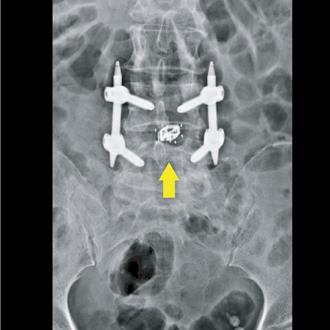

腰痠背痛腳麻木?小心是腰椎滑脫 新手術助婦重獲新生

一位年近70歲婦人因腰椎痠痛、左下肢無力及麻木不堪,趕緊就醫被診斷為腰椎滑脫所致,醫師表示透過新式撐開型支架,可有效改善痠麻痛困擾,且支架體積小、對肌肉、骨骼傷害輕微,因此該名婦人手術隔天就可下床,恢復正常生活。